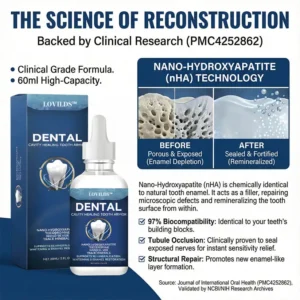

Modern research proves that enamel behaves differently when mineral loss is addressed early—before the pain, before the drilling, and before the damage becomes irreversible.

The question changed from “How do we remove decay?” to: “What if we could replace the minerals enamel is losing before the cavity even forms?”

This shift led scientists to a breakthrough discovery: Nano-Hydroxyapatite. By reducing the tooth’s natural building blocks to a microscopic scale, we can finally “refill” the porous areas of a tooth before they collapse. This is the science that turns the “permanent” process of decay into an interrupted process of repair.